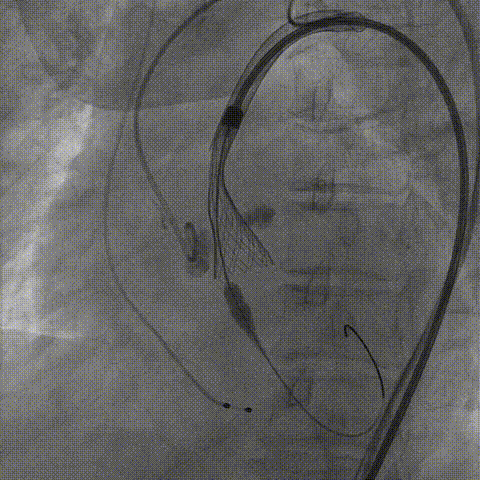

TaurusNXT植入过程

手术使用Z-Med 20mm球囊预扩两次,植入AV23 TaurusNXT主动脉瓣,Snare圈套器协助输送系统过弓、过瓣,120次/分起搏频率下,在左右重合位影像下释放瓣膜达到工作位,造影显示位置偏深,完全回收两次后释放达工作位,造影显示位置仍然不理想,之后第三次使用部分回收,精准释放瓣膜,之后使用Z-Med 20mm球囊后扩张两次。术后即刻超声心动图评估显示瓣膜位置良好,微量瓣周漏,主动脉瓣口峰值流速为1.90m/s,平均跨瓣压差为8mmHg,有效瓣口面积 1.60cm²,血流动力学指标理想。

术中影像

Snare协助输送器跨瓣